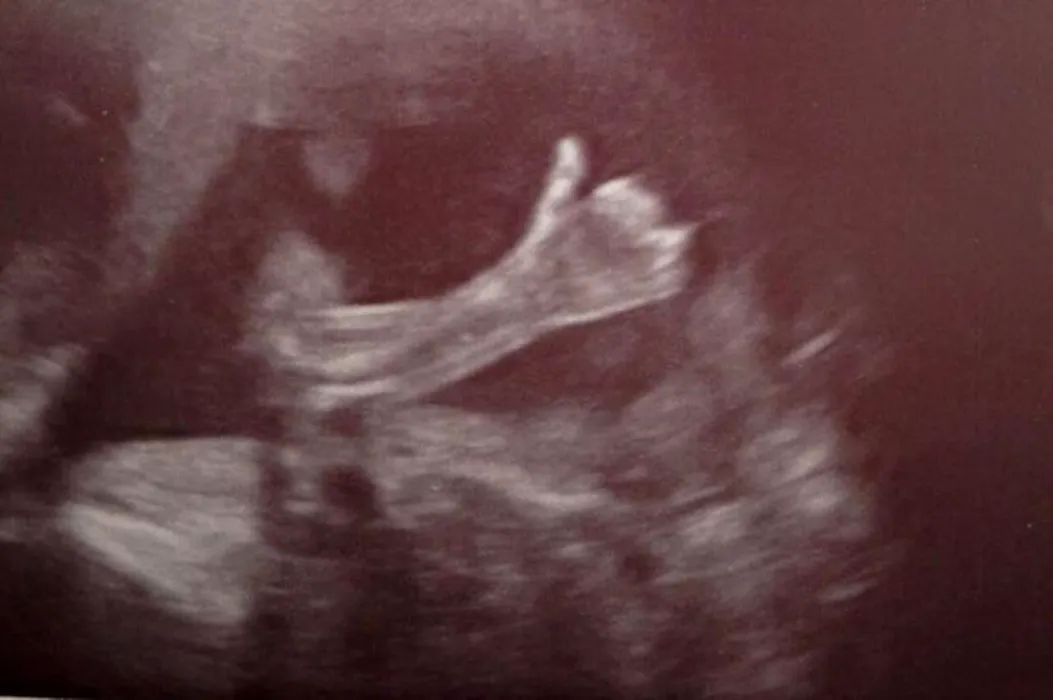

Au mers la un control de rutină, dar au avut parte de o experiență unică când a văzut ecografia